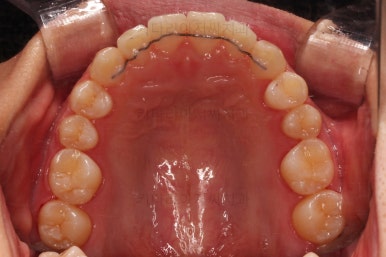

초진 시 입안의 모습이에요.

위아랫니가 모두 삐뚤어요.

특히 앞니가 삐뚤고 위아래 앞니가 고르게 덮여있는게 아니라 뒤죽박죽 엉켜있어서 치아의 마모도 굉장히 많이 되어있는 상태였어요.